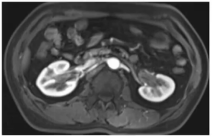

为明确IgG4相关性疾病的累及范围,进一步完善多部位影像学检查:

(2)下腹部增强核磁:显示右侧肾盂增厚,输尿管上段周围软组织增厚、管腔狭窄。